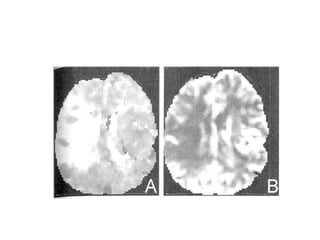

CT Scan

• May be normal within the first 12 hours

of Arterial Ischaemic Stroke.

• Bland

lesion

infarct appearsas

low-density fitting

a vascular

territory.If

hemorrhage occurs additive hyperdense

area are seen.

CT spiral angiography :It identifies the AV

malformation and aneurysm.

•

RADIOGRAPHIC FEATURES

MRI and MRA : MRI is better than CT scan as

• It is more sensitive than CT in detecting small and multiple

infarcts.

In posterior fossa, it is more sensitive than CT scan

• More sensitive at detecting hemorrhagic conversion of

infarct.

MRA can be performed at the same time. It is able to visualize

the flow in major cerebral, vertebral and external carotid

arteries.